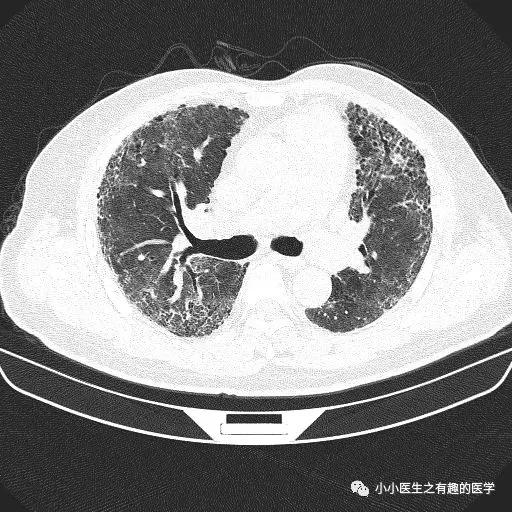

经典的间质性肺炎,就是一张网!

1.胸膜下2.网格状很多间质性肺炎,都有这个特征,是间质性肺炎的入门知识,也是很重要的知识。